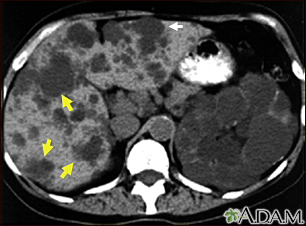

Kidney and liver cysts - CT scanBackKidney and liver cysts - CT scanThis abdominal CT scan shows cysts in the liver and kidneys (polycystic disease). The liver is the large organ on the left side of the screen. The dark spots in the liver are cysts. E-mail FormEmail ResultsName:Email address:Recipients Name:Recipients address:Message: